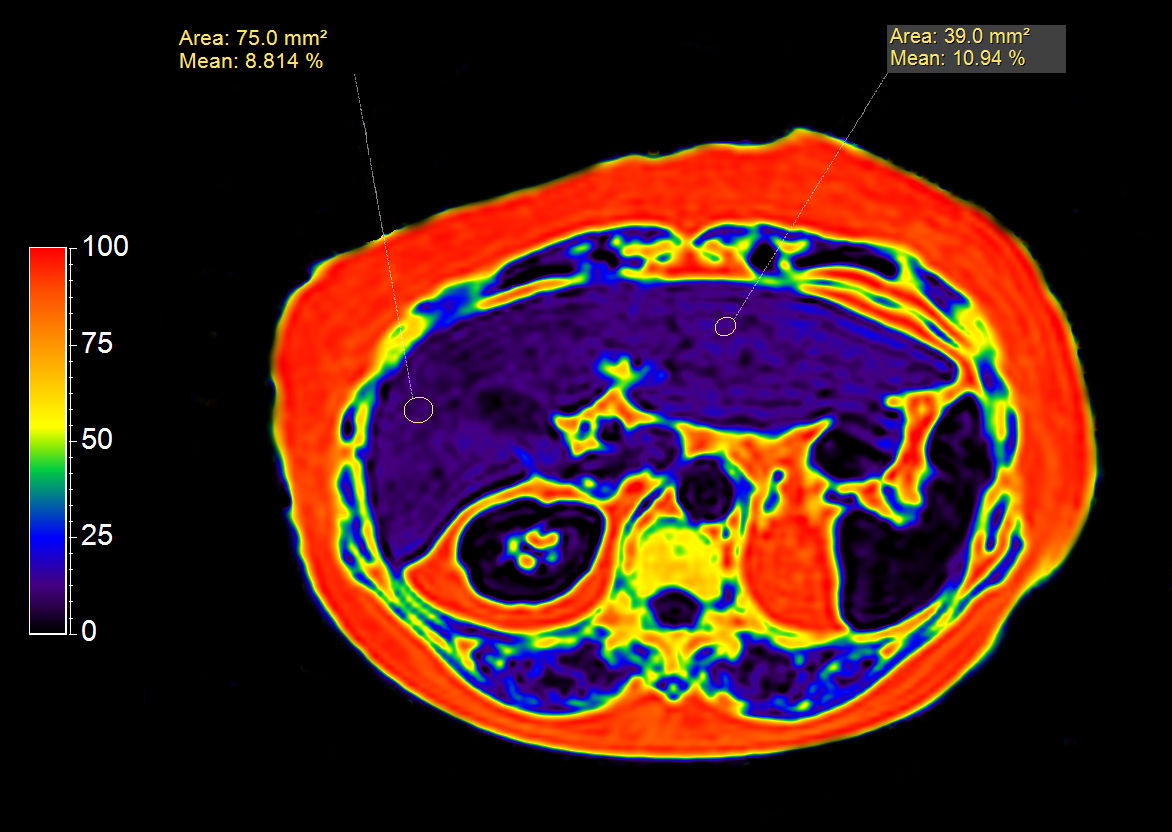

mDIXON XD Quant (Fat Fraction Map)

Liver ExamCard including single breath hold 3D mDIXON Quant for non-invasive liver fat quantification of the whole liver with high accuracy (± 3.5%) and reproducibility (± 1.4%)1. And MR Elastography for a non-invasive assessment of differences in tissue stiffness of the liver. Image processing is fully integrated at the scanner with automated calculation of Elastograms, reflecting tissue stiffness in kPa and statistical confidence map for reliability assessment.